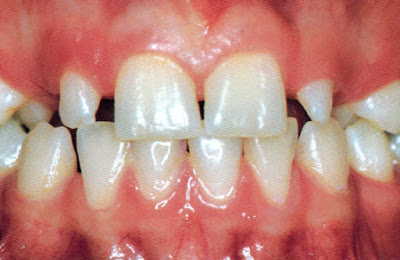

L’amélogénèse imparfaite, relativement fréquente, touche surtout les dents temporaires.

Amélogénèse imparfaite de la deuxième dentition (universitederennes1).

Amélogénèse imparfaite de la deuxième dentition (Université de Rennes 1).

Amélogénèse imparfaite du groupe incisivo-canin lactéal chez un enfant de 18 mois.